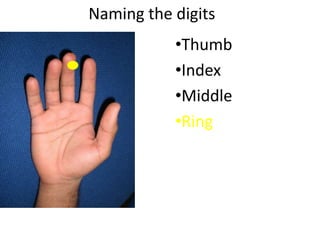

- Naming the bones, joints, tendons, nerves and skin landmarks of the hand and wrist.